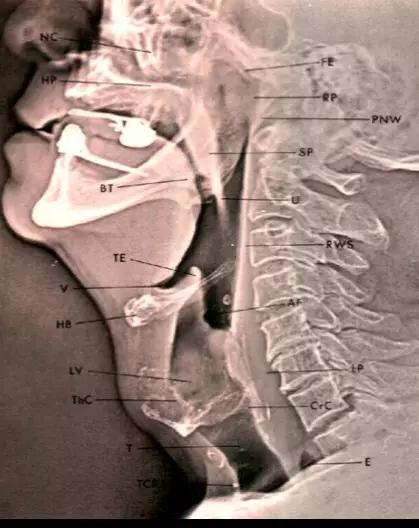

四、正常影像表现1、 X线检查

侧位片可清楚显示会厌溪、会厌、声门上区、声门下区

正位体层摄影可清楚显示喉前庭、喉室、声带(真声带)和声门下区结构,在呼气、吸气、闭气、发音时可见声带的活动度及其形态。